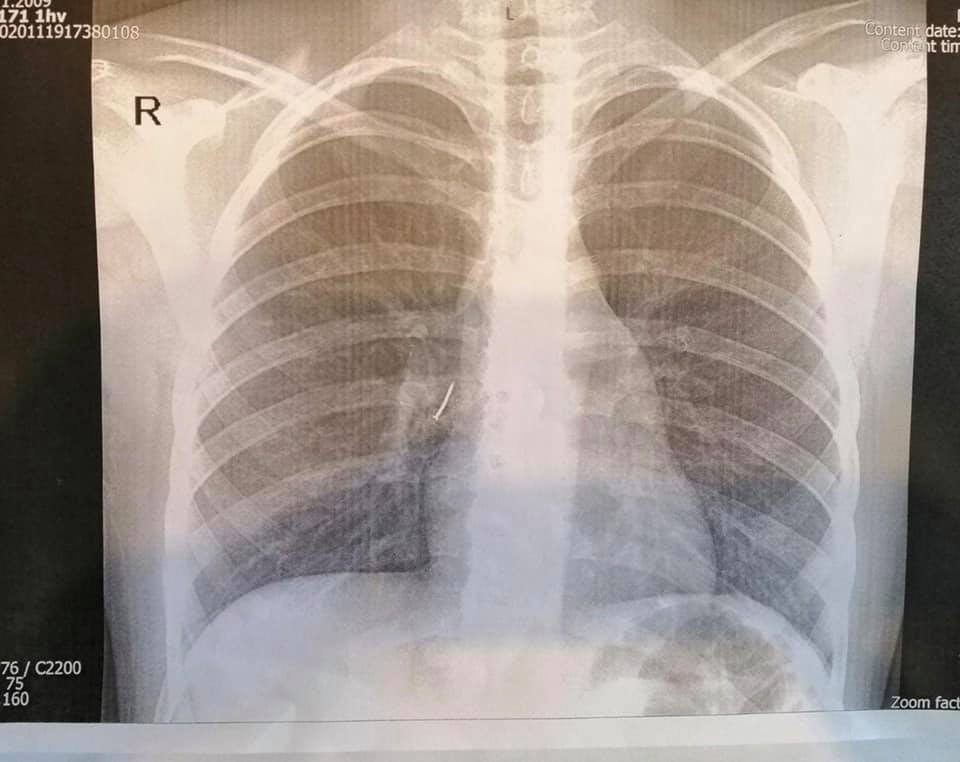

Маленька пацієнтка з канцелярським цвяхом потрапила до нас в ОХМАТДИТ сьогодні вночі. Її до нас привезла швидка з Ходорівської міської лікарні. Дитині зробили рентген-знімок і слова дівчинки про стороннє тіло у бронху підтвердилися – на знімку чітко видно цвях.

“Ми виконали ригідну трахеобронхоскопію під наркозом. Спеціальними ендоскопічними інструментами – щипцями під оптичним контролем – з правого проміжного бронха дитини ми дістали канцелярський цвях з пластмасовою частиною і гострим вістрям. То було непросто, адже пластмасова частина цвяха повністю перекрила бронх так, що нижня доля правої легені майже не функціонувала”, – розповів Олександр Колодій, який займався порятунком дитини.